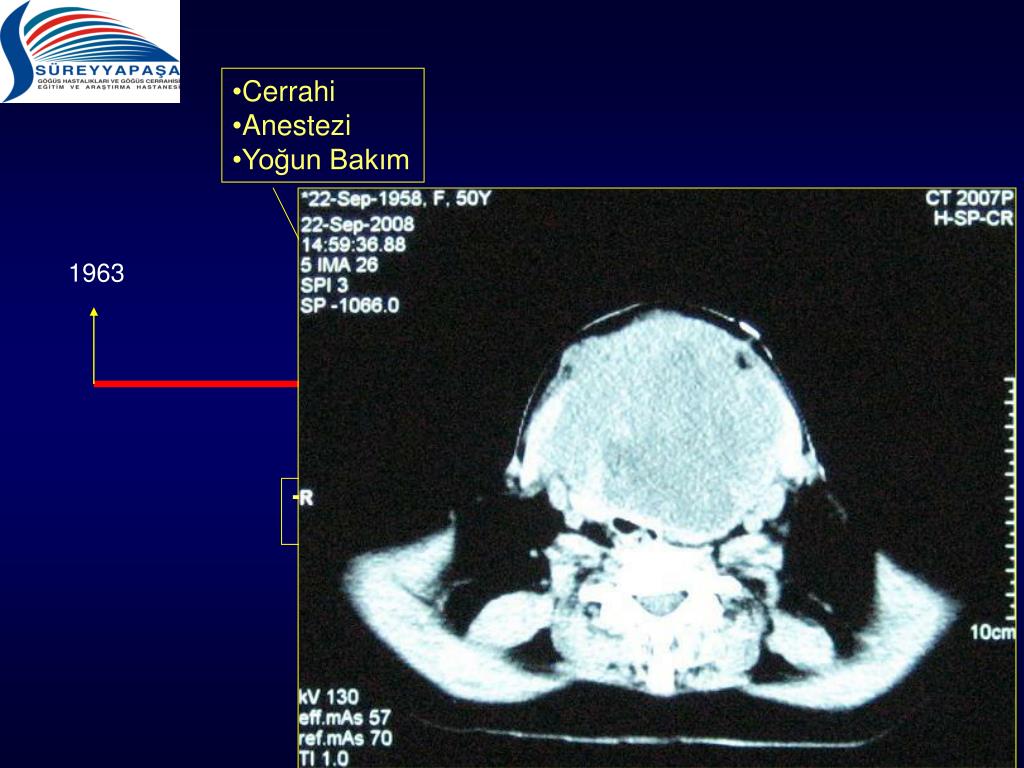

15. Cerrahi • Anestezi • Yoğun Bakım 1963 1983 2007 2009 2006 Teknik Hazırlık

16. Cerrahi • Anestezi • Yoğun Bakım 1963 1983 2007 2009 2006 Teknik Hazırlık

17. Cerrahi • Anestezi • Yoğun Bakım 1963 1983 2007 2009 2006 Teknik Hazırlık

18. Cerrahi • Anestezi • Yoğun Bakım 1963 1983 2007 2009 2006 Teknik Hazırlık

19. Cerrahi • Anestezi • Yoğun Bakım 1963 1983 2007 2009 2006 Teknik Hazırlık

20. Cerrahi • Anestezi • Yoğun Bakım 1963 1983 2007 2009 2006 Teknik Hazırlık